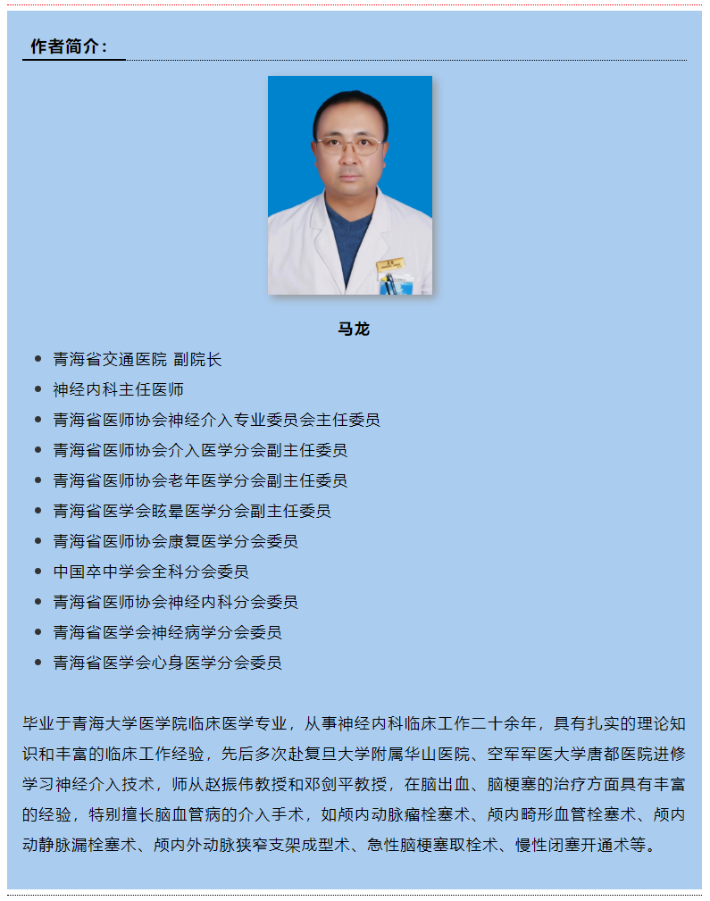

3D处理后可见大脑中动脉下干重度狭窄

3D处理后可见大脑中动脉下干重度狭窄

3D处理后不同角度显示大脑中动脉下干重度狭窄